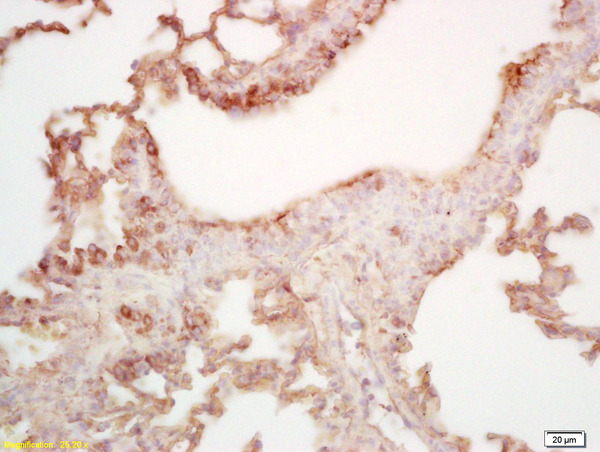

IHC-P analysis of mouse lung tissue using GTX51793 MAL2 antibody.

Dilution : 1:200